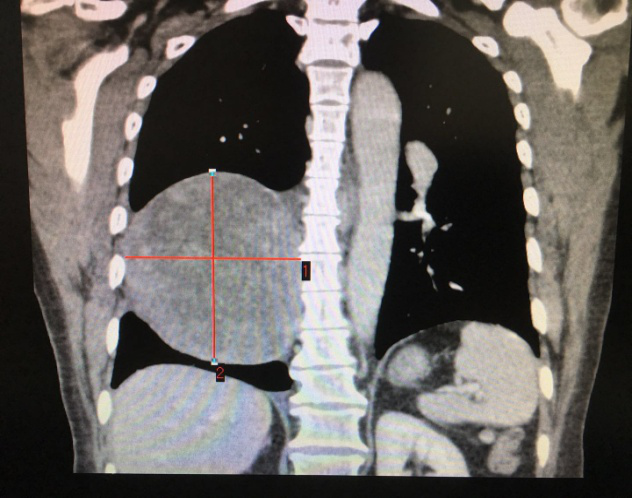

患者CT影像 (标记处为肿瘤)

李旭主任仔细为患者查体,经过严密的病情分析后,考虑肿瘤巨大,侵犯心包和下肺组织,决定先行肺穿刺,排除其他恶性肿瘤。最终穿刺病理显示,陈阿姨患的是神经鞘瘤,这让李主任松了一口气:“还有手术的机会!”。